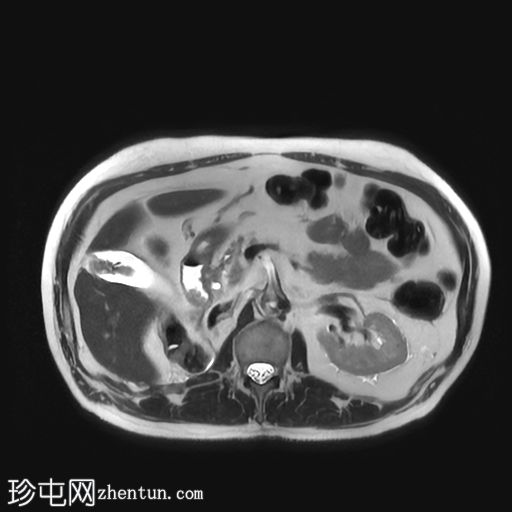

冠状位

行CT检查以进行分期。已知肾细胞癌。已行右侧根治性肾切除术和左侧肾上腺切除术。胆囊内可见强化物质,提示胆囊底部血管受累。骨窗下胆囊内未见钙化灶。影像表现提示胆囊转移。